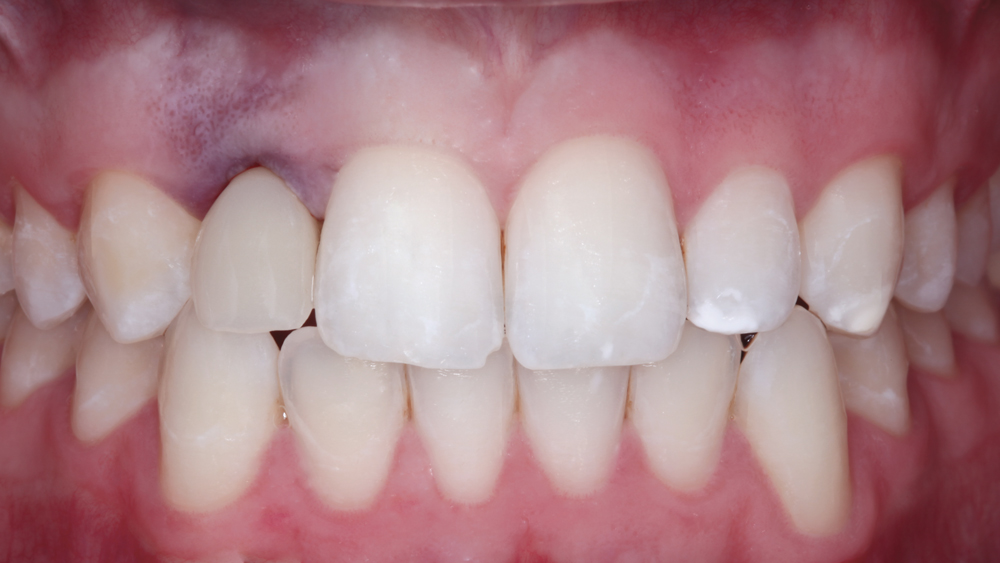

The following case illustrates the efficient, straightforward clinical workflow for placing Hahn Tapered Implants via guided surgery. A digital treatment plan is developed in which a 3.5 mm implant is positioned to support the ideal prosthetic outcome. An immediate provisional crown is designed in concert with the surgical guide and delivered at the time of surgery, helping to produce a predictable, highly esthetic restoration for a demanding case in the smile zone.